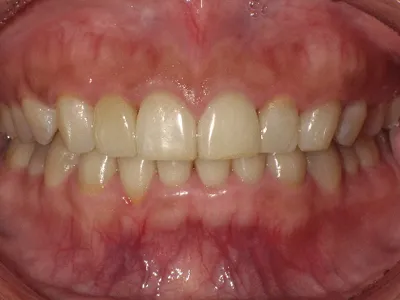

症例2

before

after

| 主訴 | 前歯が噛みづらい |

|---|---|

| 治療内容 | 矯正と奥歯のセラミック治療 |

| 治療期間 | 1年半 |

| 費用 | 660,000円(税込) |

| リスク・副作用 | 矯正期間中一時的に染みる症状や咬合痛が出ることがまれにあります |